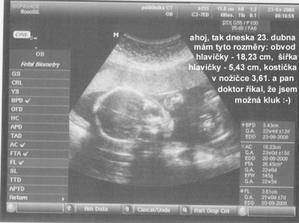

Těhotenství

Jak to začalo? S manželem jsme chtěli miminko víc než rok a pak když jsme si řekli, že nám pomůže změna prostředí a přestali na to myslet najednou to bylo tady.

Když jsem mu kolem půlnoci 28.12. donesla pozitivní těhotenský test oba jsme měli velikánskou radost. Ještě v pondělí 31.12. jsme narychlo zašli k mé gynekoložce a ta nám to již jen potvrdila. Nadělili jsme si pod stromeček ten nejhezí dáreček.